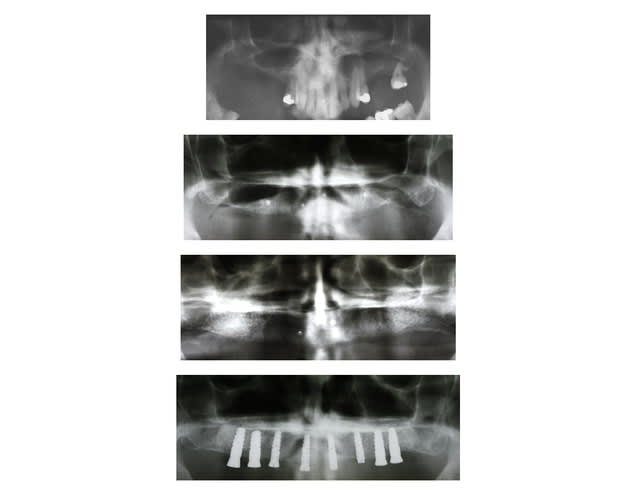

Sujet proche du fil...

Exo du haut + complet immédiat (mars 2009)

Comblement sinus bi-lat (mai 2009)

Pose de 8 implants (avec guide Simplant)(4 nov 2009)

--

Céramik